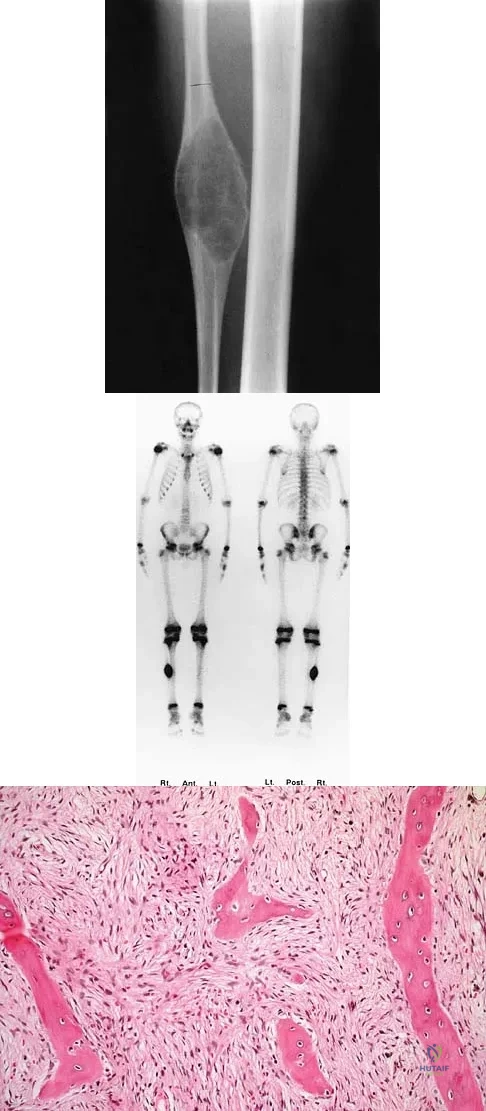

A 13-year-old boy has pain and a firm mass in his left knee. A radiograph and MRI scan are shown in Figures 2a and 2b, and a biopsy specimen is shown in Figure 2c. Based on these findings, what is the most likely diagnosis?

The most likely diagnosis is osteosarcoma. The imaging studies show an aggressive primary tumor of bone, and the histology slide shows a typical chondroblastic osteosarcoma, with osteoid deposited along the surface of bone trabeculae. Ewing's sarcoma histologically consists of small round blue cells. Osteochondroma and periosteal chondroma can occur near the knee but have different radiographic and histologic patterns. Chondrosarcoma rarely occurs in children. Simon M, Springfield D, et al: Osteogenic sarcoma: Surgery for Bone and Soft Tissue Tumors. Philadelphia, PA, Lippincott Raven, 1998, p 267.

Wold LA, et al: Atlas of Orthopaedic Pathology. Philadelphia, PA, WB Saunders, 1990, pp 14-15.